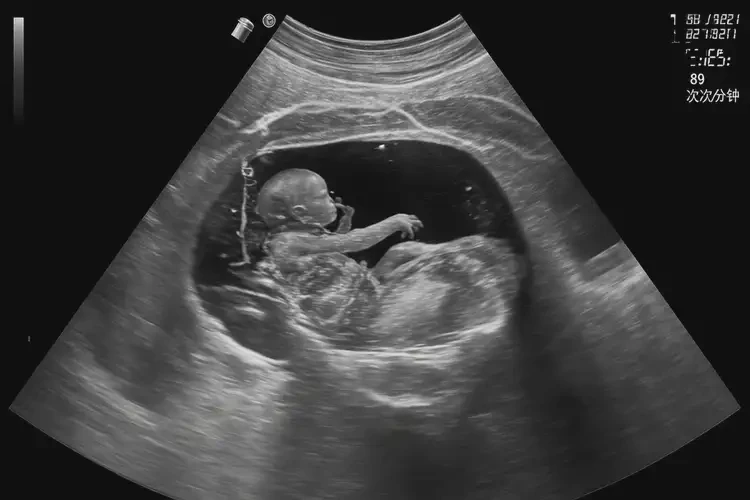

胎心率89次/分鐘在孕23周3天可能存在風(fēng)險(xiǎn)。胎心率是評(píng)估胎兒健康狀況的重要指標(biāo),正常范圍通常在110-160次/分鐘。89次/分鐘低于正常范圍,可能表示胎兒存在缺氧或其他健康問(wèn)題。

胎心率89次/分鐘在孕23周3天可能存在風(fēng)險(xiǎn),需要及時(shí)就醫(yī)進(jìn)行評(píng)估和處理。通過(guò)定期產(chǎn)檢、健康生活方式和避免高危因素等預(yù)防措施,可以減少胎兒健康問(wèn)題的風(fēng)險(xiǎn)。